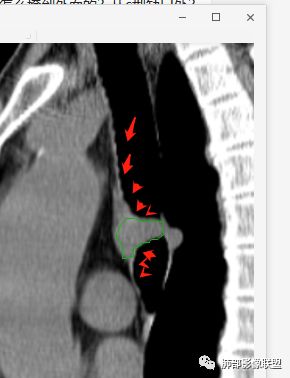

南边分析:针对本例,病灶跨气管壁内外生长,常规跨内外的有:恶性肿瘤为主,其次就是神经源性、平滑肌瘤;常规的思维:跨内外就要看结构的变化气管的优势在于软骨相对密度高,而且成C型

我们如何分析这个病例?冠状位:软骨密度稍高;病灶区软骨部分区域不连续,外围连续,提示病灶推移为主,不是破坏为主;如果破坏,应该这些软骨显示不清,移位不明显

病灶从软骨见推移开,跨内外,因此定在良性。恶性是侵犯,破坏为主,如果破坏,应该这些软骨显示不清,移位不明显,不是推移为主这例病变定在良性,我们就要考虑:1、软骨之间的平滑肌来源;2、神经源性

南边:

南边:高密度软骨在这两点上停了

南边:挤过去了,说明是从软骨间过去的

尘缘:@Shelia,部分是向前推,部分是向后推的。这个地方应该还有向后推的;肿物是从向前推与向后推这个间隙跨软骨的。

南边:需要用连续的窄窗观察。

病例小结      气管神经鞘瘤属于罕见的气管良性肿瘤,一般气管良性肿瘤或腔内或腔外生长的结节样改变,恶性肿瘤呈腔内外生长,但本例肿块向腔外生长,呈“冰山样改变”,即肿瘤的腔内部分较小而腔外部分较大,无周围组织侵犯。因此肿瘤腔内外生成不能作为鉴别气管良恶性肿块的绝对依据。        因此冠(矢)状位多平面观察、软骨是否破坏、气管壁有无增厚等细节观察,对于鉴别气管肿块良恶性有重要的参考性。

1.气管隆凸上右前壁不规则结节影,部分突入腔内,南边老师观察有推挤软骨环“破土而出”的形态特征。注意没有沿气管粘膜表面生长蔓延的生物学行为。